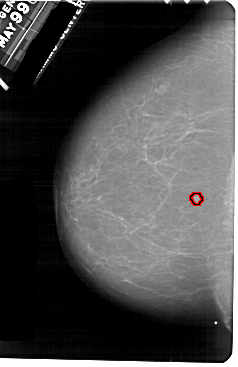

A_1754_1.LEFT_MLO

LEFT_MLO LINES 5341 PIXELS_PER_LINE 3361 BITS_PER_PIXEL 12 RESOLUTION 43.5 OVERLAY

FILE: A_1754_1.LEFT_MLO.OVERLAY

TOTAL_ABNORMALITIES 1

ABNORMALITY 1

LESION_TYPE MASS SHAPE ROUND MARGINS CIRCUMSCRIBED

ASSESSMENT 3

SUBTLETY 4

PATHOLOGY BENIGN

TOTAL_OUTLINES 1

BOUNDARY